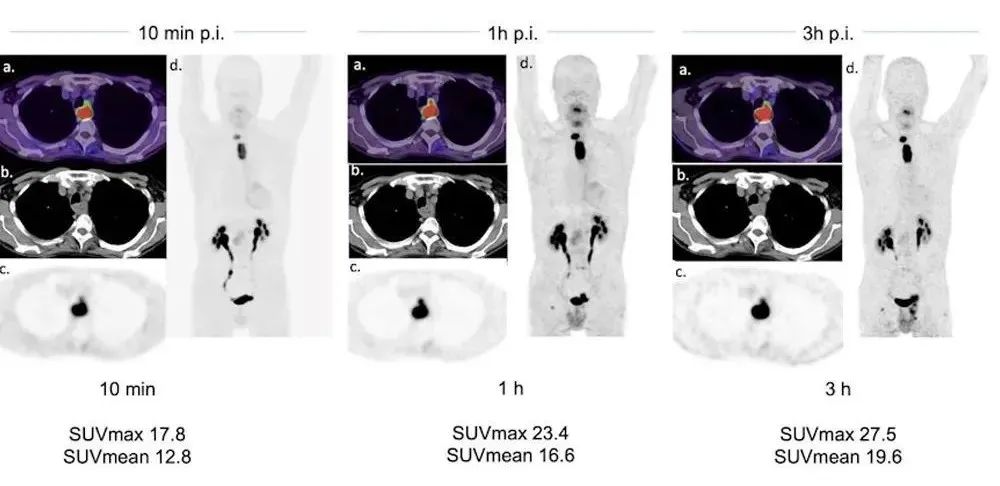

一例63歲的食道癌患者。在明確的放化療之前,進行FAPI-46 PET/CT用于照射計劃。在注射后10分鐘、1小時和3小時進行FAPI-46 PET。圖片由《核醫(yī)學(xué)雜志》提供。

為了解決知識缺口,Giesel和他的同事回顧性分析了43例不同癌癥診斷的患者的結(jié)果,這些患者在注射示蹤劑后10分鐘、1小時和3小時接受了Ga-68 FAPI-46 PET/CT掃描。他們根據(jù)標(biāo)準(zhǔn)化攝取值(SUVmean和SUVmax)和腫瘤與背景的比率(TBR)來確定患者腫瘤中的示蹤劑攝取。

FAPI-PET掃描顯示了43名患者的171個病灶。研究小組發(fā)現(xiàn),比較不同時間點的所有損傷,平均SUVmax在10分鐘時最大(8.2),在施用示蹤劑后1小時(8.15)和3小時(7.6)略有下降。

此外,平均SUVmax在原發(fā)病灶、淋巴結(jié)轉(zhuǎn)移和遠(yuǎn)處轉(zhuǎn)移中具有相似的模式。TBRs在三個時間點上也沒有顯著性差異。

最終,盡管這是一項小型研究,但由于10分鐘和1小時之間的檢測率相似,作者建議注射后10至20分鐘是診斷PET成像采集的最佳時間點。